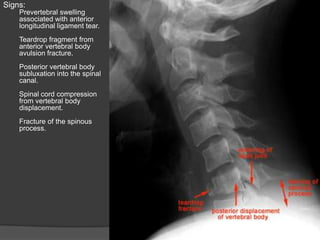

Signs:

Prevertebral swelling

associated with anterior

longitudinal ligament tear.

Teardrop fragment from

anterior vertebral body

avulsion fracture.

Posterior vertebral body

subluxation into the spinal

canal.

Spinal cord compression

from vertebral body

displacement.

Fracture of the spinous

process.